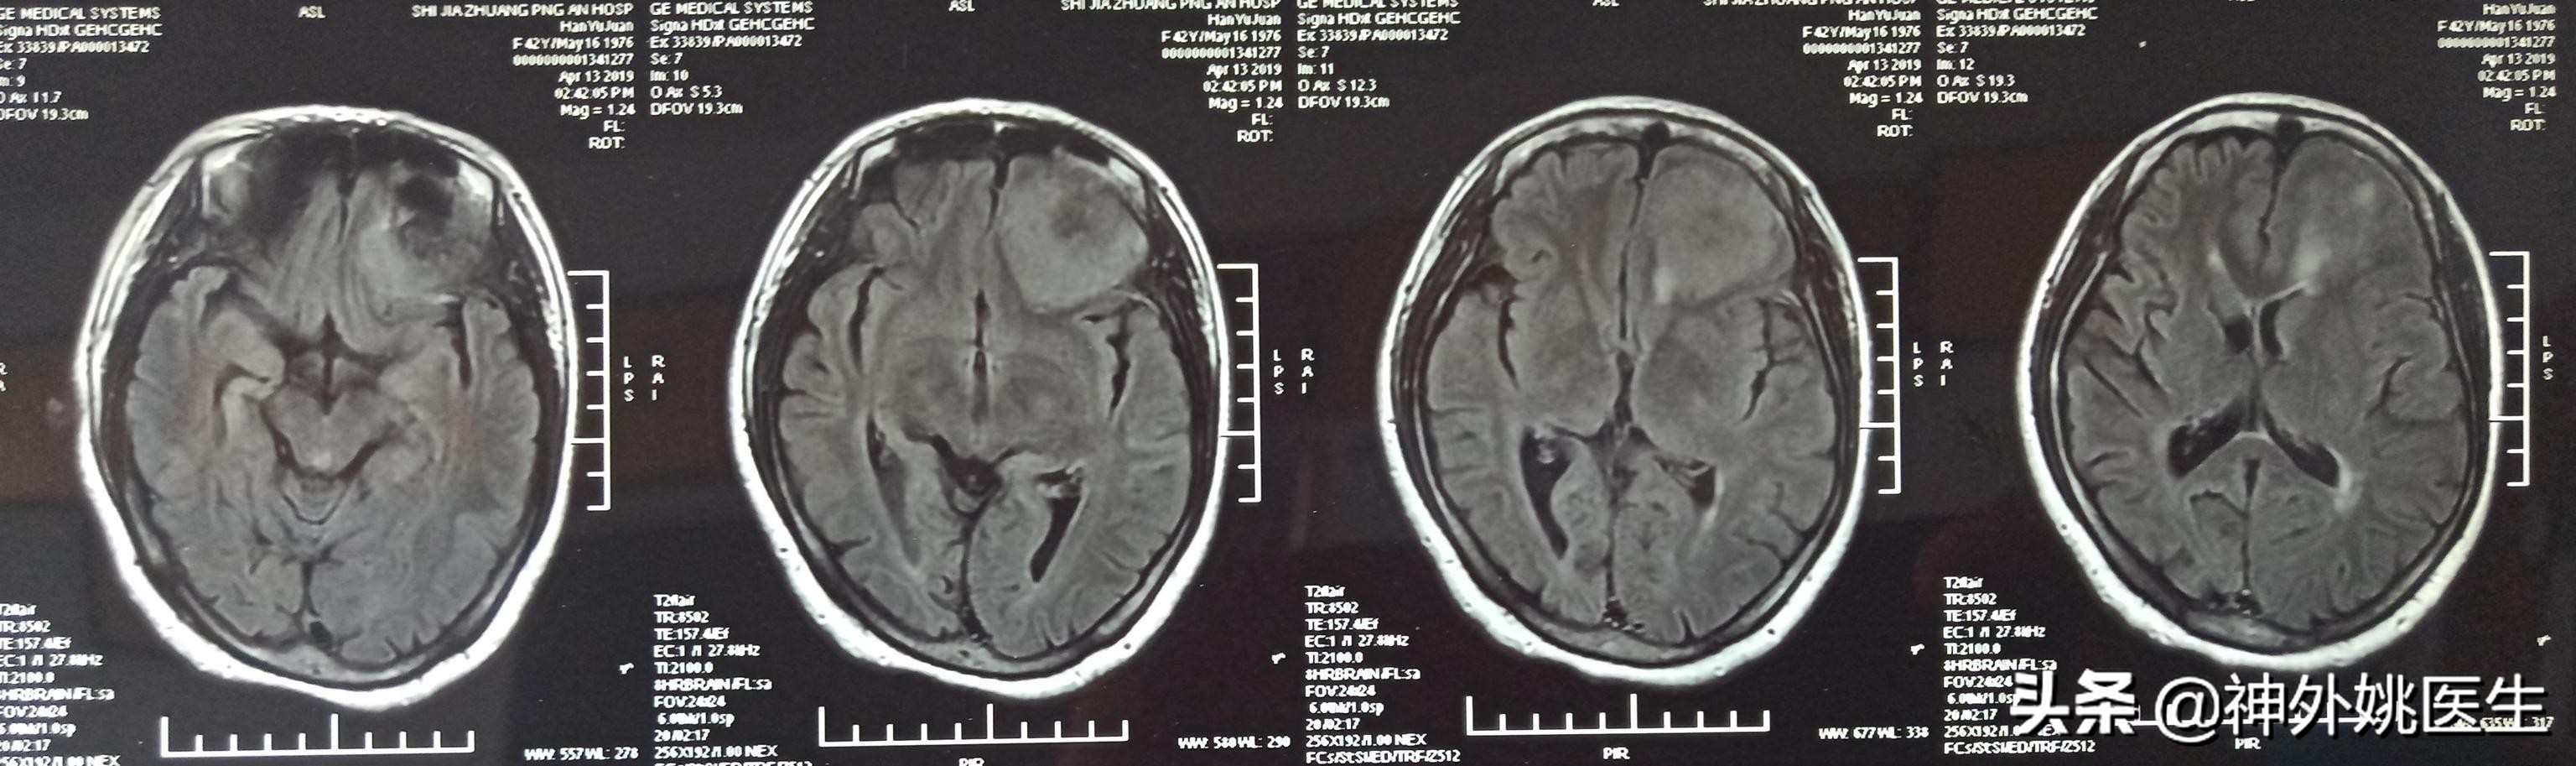

头MRI检查:1、左额部脑膜瘤。2、左侧放射冠区腔隙性脑梗死。(图3-7)

图6 增强扫描可见病变呈不均匀强化。

图7 病变基底位于颅底硬膜,可见脑膜尾征,病变大小约3.8cm x 4.1cm x 2.9cm。